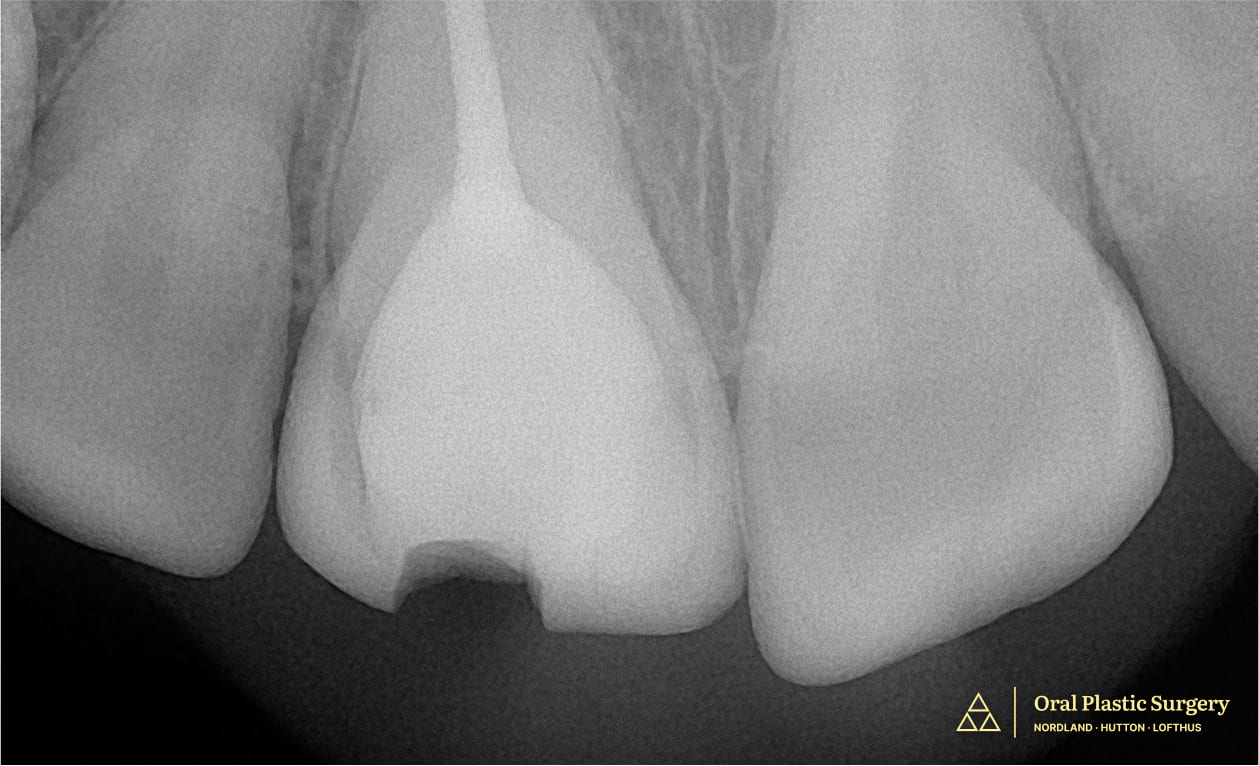

At her first appointment, a thorough clinical exam and X-rays revealed there wasn’t enough remaining structure to support a lasting restoration.

Showing a large filling and minimal natural structure, making the tooth non-restorable.

Tooth #8 shows a visible fracture, indicating structural compromise and the need for further evaluation and treatment